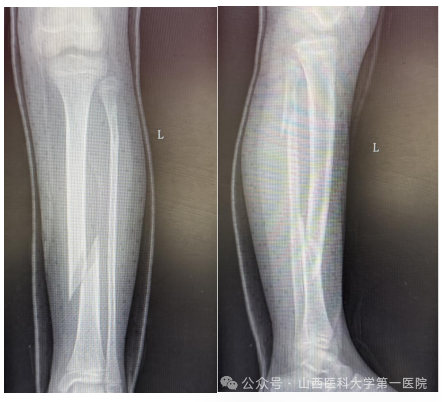

9岁女孩王某某在家中不慎滑倒后导致左小腿胫腓骨螺旋骨折,家长焦急万分,为了获得更好的治疗来到东京热

骨科门诊,杨自权主任详细评估患者病情后收入病房继续治疗。

儿童胫腓骨骨折多因外伤导致,因儿童骨膜厚、愈合快、塑性能力强,因此微创治疗可减少手术创伤、降低并发症。但王某某为左侧胫腓骨螺旋骨折,骨折断端移位大、稳定性差,若行微创手术复位无疑增加了手术难度。杨自权主任团队分析病情后,考虑患者仅为9岁女孩,最后计划使用闭合复位儿童弹性髓内钉(ESIN)内固定术,微创手术瘢痕小,在保留美观的同时尽可能减少对儿童骨骼生长发育的影响。